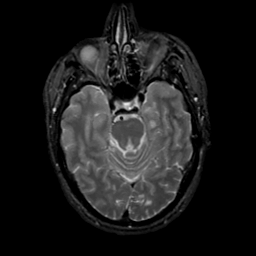

MR Study #20 October 6, 1991 -- Slice #17

[Home][Help][Clinical][Tour 1][Tour 2] Slice 17